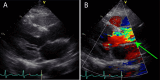

Figure 2. Preoperative echocardiography.

(A) Long-axis image of the left sternal border. (B) The mosaic flow was observed at the aortic valve (green arrow).